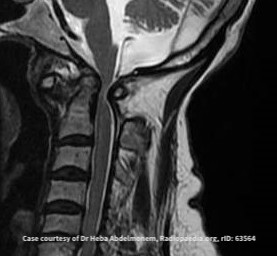

下圖為頸椎第一節向前滑脫,造成脊髓神經壓迫的例子。

由於第一節頸椎滑脫太靠前,壓到脊椎神經造成神經壓扁,由於此處為頸椎高位,可能影響頸椎神經往下傳遞的神經訊號,輕度可能只有後頸痛的症狀,嚴重一點可以包括上肢的無力或感覺異常,甚至可以從胸下失去知覺,影響呼吸肌肉,甚至全身癱瘓無力。